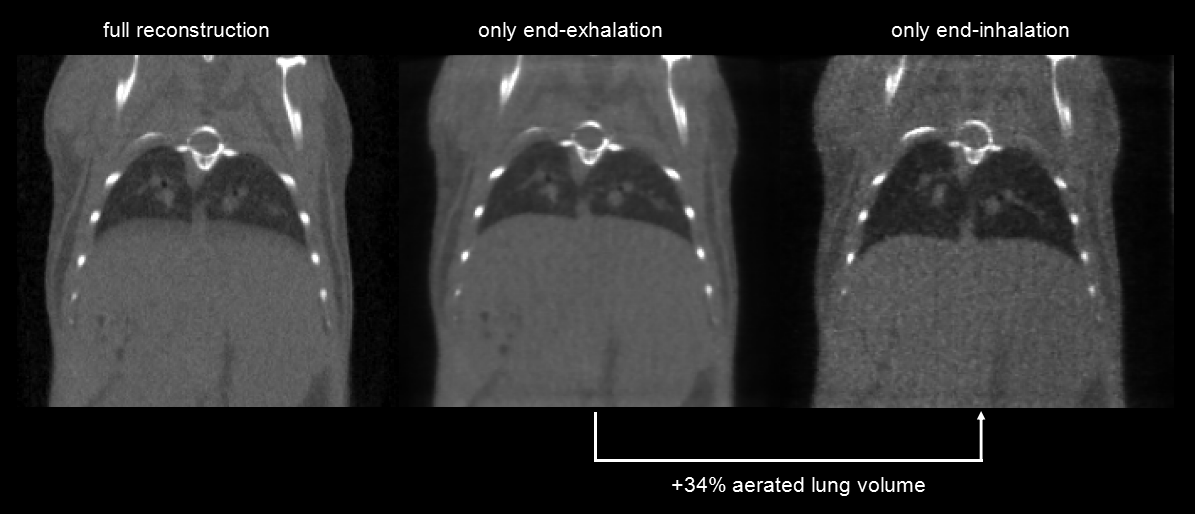

呼吸門控:超高時(shí)間分辨率(10ms),4min,390mGy。左圖:整體整合的圖。中圖:呼氣結(jié)束時(shí)的圖,右圖:吸氣結(jié)束時(shí)的圖,兩者顯示肺的容積相差34%。

圖13. 呼吸門控.png